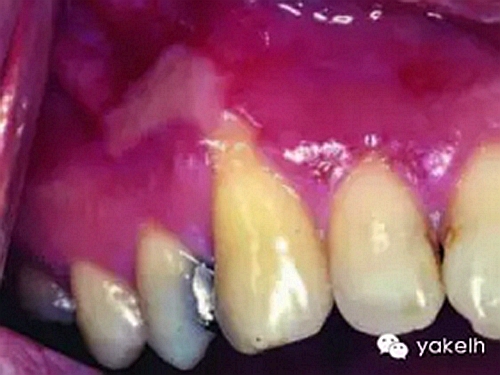

¤¤現(xiàn)在臨床使用的樹脂基類牙科材料的潛在危害性尚不確定,迄今的觀點(diǎn)是由于合成物的組成成分較多,包括一些未明確的物質(zhì),所以產(chǎn)品的生物相容性可能不同。但是由于這類材料的主要成分(BISGMA、TEGDMA、HEMA)和合成的過程是一樣的,因此包括正畸粘結(jié)材料在內(nèi)的樹脂基牙科材料的基本生物相容性是相似的。體外實(shí)驗(yàn)顯示在樹脂聚合后不久,其中的成分就可以釋放到口腔中并達(dá)到一定濃度,引起口腔黏膜的刺激性反(圖10.7),這種反應(yīng)一般是短期的,釋放量隨著時(shí)間的延長而減少。有關(guān)這方面的病例報(bào)道是很少見的,從理論上而言黏膜的刺激反應(yīng)可能被忽視了,忽視的原因可能是反應(yīng)不重或者被誤診。迄今仍沒有文獻(xiàn)報(bào)道在粘結(jié)全口固定矯正器后,殘留物質(zhì)的釋放量,當(dāng)然研究的結(jié)果也不能直接應(yīng)用于臨床。雖然最終暴露于口內(nèi)的粘結(jié)材料相對較少,但是在粘結(jié)過程中患者所接觸的材料和底漆的總量是高于粘結(jié)單個(gè)或幾個(gè)修復(fù)體的量。而且正畸粘結(jié)劑中的樹脂含量顯著高于牙修復(fù)材料,后者含有60%~80%的無機(jī)填料用來改善材料的耐磨性。現(xiàn)今粘結(jié)全口固定矯正器的正畸患者在治療中及治療后,到底有多少粘結(jié)材料被釋放到口內(nèi)還不知道。

圖10.7 13齦緣處復(fù)合樹脂修復(fù)24h后,鄰近局部出現(xiàn)刺激性黏膜反應(yīng)。